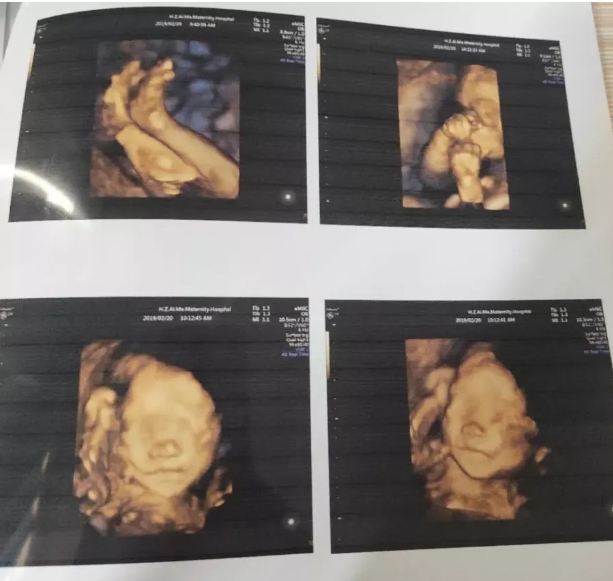

胎儿心脏彩超

胎儿心脏彩超是胎儿心脏产前超声初步检查,主要采用超声成像技术及彩色多普勒血流成像技术,观察胎儿心脏的大体形态结构,以便对大部分胎儿先天性心血管结构畸形进行可靠的产前筛查和评估。